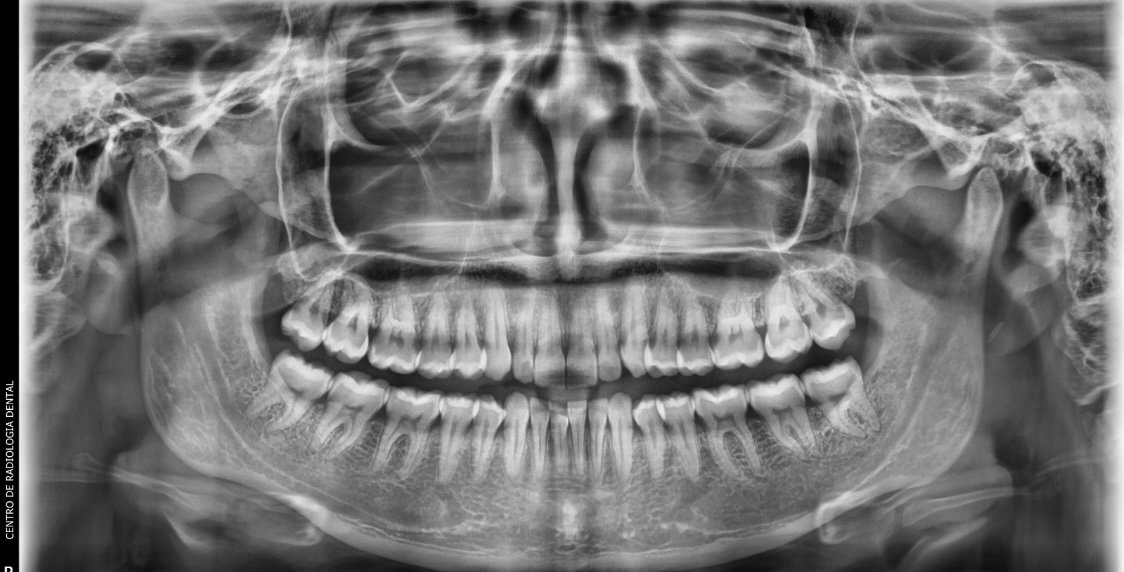

Imagen de Radiografía Panorámica (Ortopantomografía)

Radiografía Panorámica (Ortopantomografía)

Una vista completa de todos los dientes, maxilares y articulaciones temporomandibulares. Esencial para valoraciones generales, planificación de ortodoncia y detección de patologías.

Costo: Consultar precio Duración: 15 min